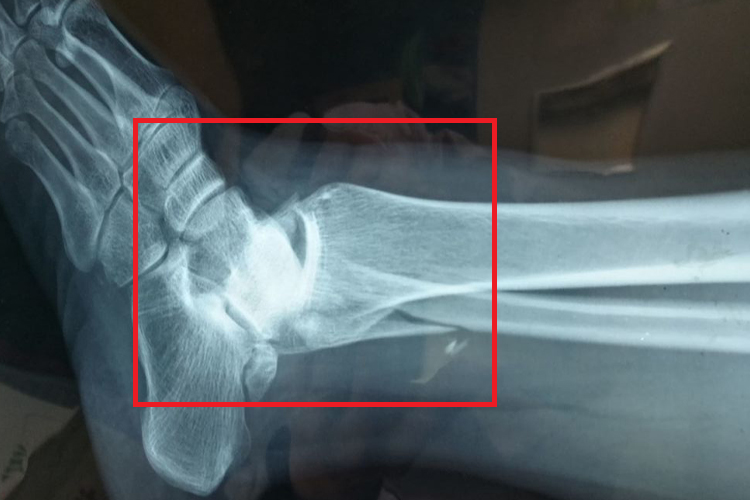

脚踝骨折的患者伤处会有明显的肿胀,局限性压痛、淤斑,出现内翻或外翻畸形,以及不同程度的活动障碍。X线可清晰显示踝部骨折情况,侧位可见前距腓韧带完全断裂,外侧韧带前束和中束断裂出现距骨倾斜。